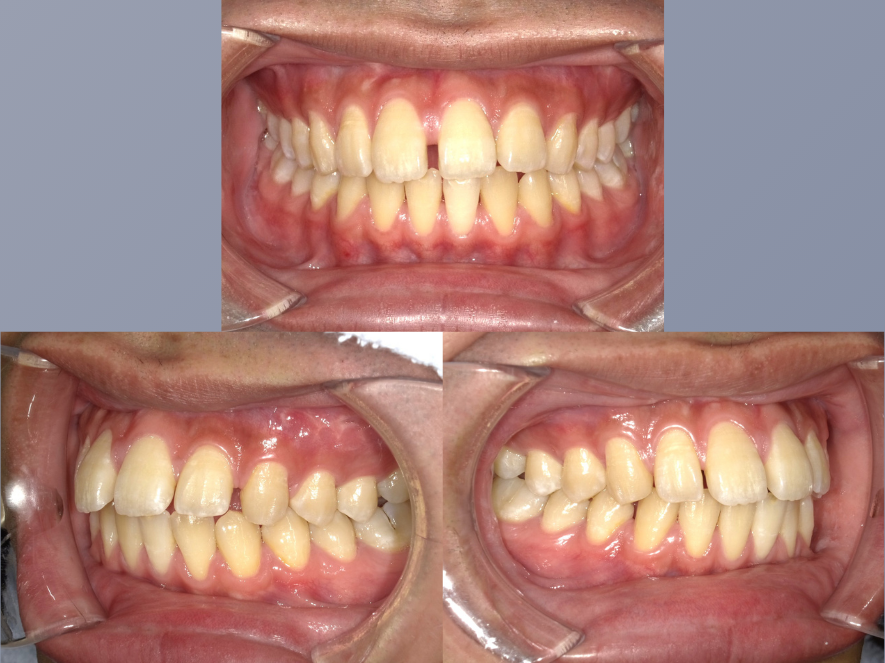

治療後

| 年齢・性別 | 20代・男性 |

|---|---|

| 主訴 | インビザラインが気になる。 |

| 期間 | 1年9カ月 |

| 費用 | 495,000円 |